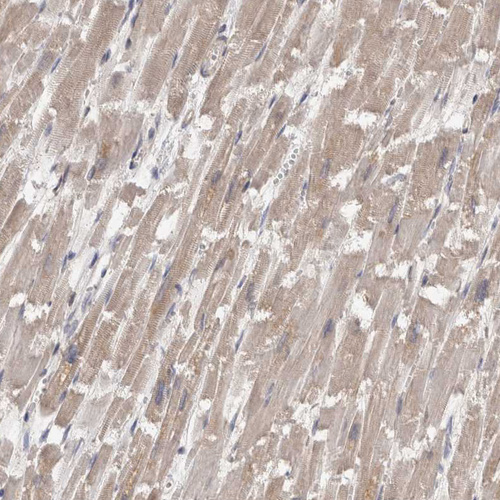

Immunohistochemical staining of human heart muscle shows moderate cytoplasmic positivity in cardiomyocytes.